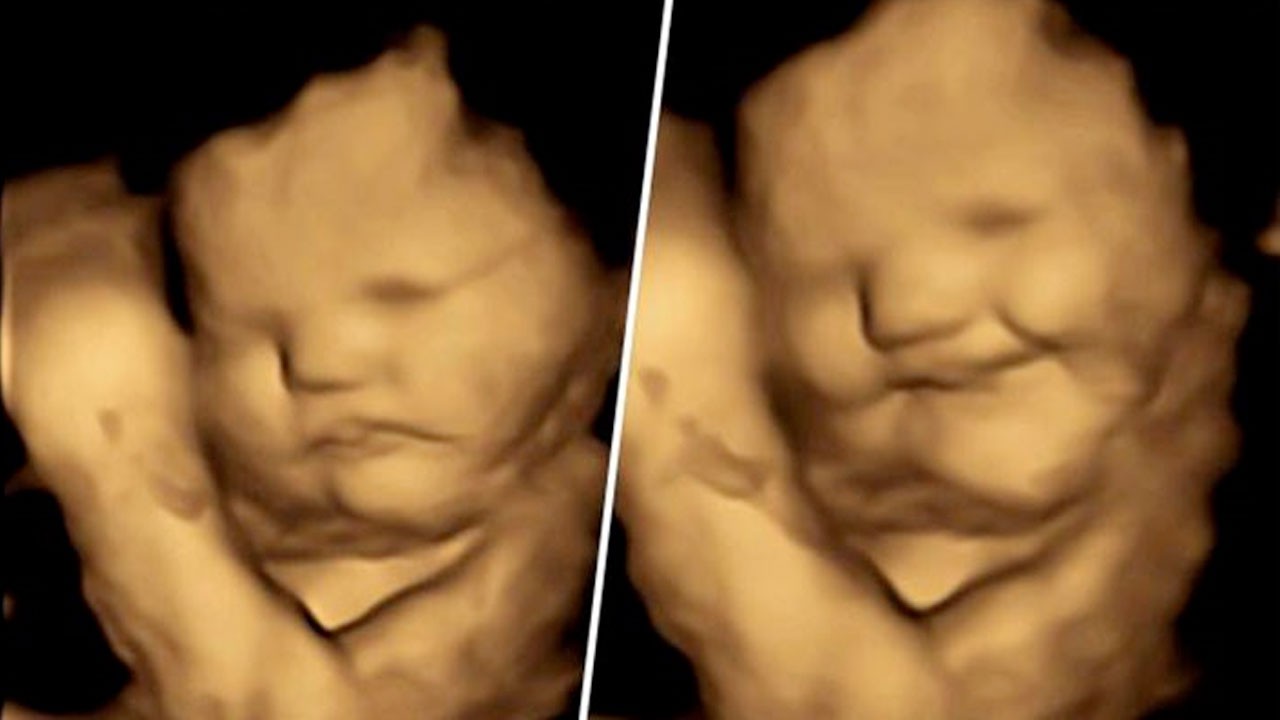

Yukarıdaki fotoğrafta bebeklerin anne karnında çekilmiş 4 boyutlu bir ultrason görüntüsü yer alıyor.

Annelerinin karnında, anne havuç sinirdiğinde daha mutlu bir yüz ifadesi gösteren bebekler adeta gülümsedi. Karalahana yendiğinde ise bebeklerin yüz ifadesi daha ağlamaklı bir yüz ifadesine dönüştü.